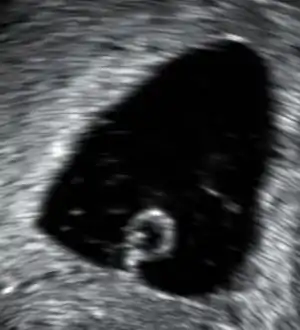

An anembryonic pregnancy (also called an "empty sac" or "blighted ovum") is a condition where the gestational sac develops normally, while the embryonic part of the pregnancy is either absent or stops growing very early. This accounts for approximately half of miscarriages. All other miscarriages are classified as embryonic miscarriages, meaning that there is an embryo present in the gestational sac. Half of embryonic miscarriages have aneuploidy (an abnormal number of chromosomes).[50]